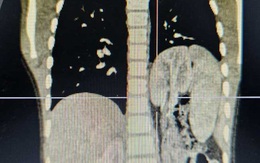

Bé trai 6 tuổi có thận ‘đi lạc’ lên lồng ngực

Bé trai T. (6 tuổi, ở Hà Nội) bị thoát vị hoành bẩm sinh, kèm theo thận lạc chỗ trên lồng ngực và phổi biệt lập.